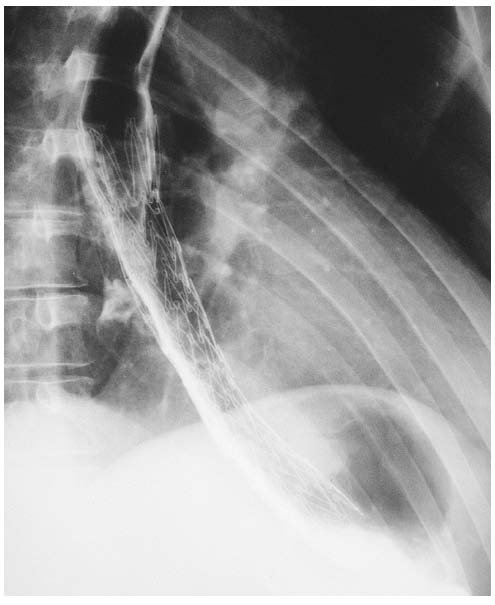

Implantovaný kovový stent při karcinomu distálního jícnu.